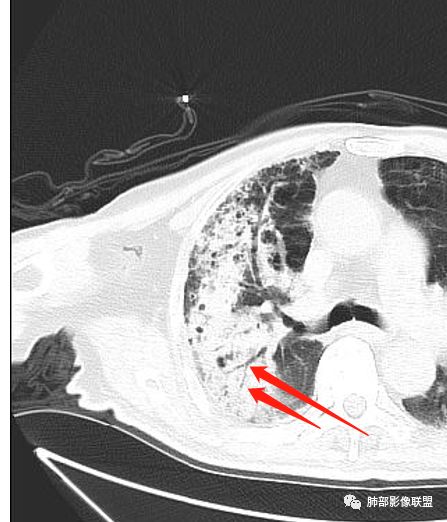

Shelia??:

老年男性,糖尿病10年,咳嗽气喘10天,肺气肿背景,右上肺大片实变影,内见虫蚀样空洞及空气支气管征,局部可见新月形空洞影,支气管局部欠光整,考虑感染性病变,结核?其内合并曲霉可能。

老年男性,糖尿病患者,右上肺大片实变,内可见多发虫蚀样空洞,右尖段近胸膜处一空洞内可见一类圆形结节影,支气管扩张,淋巴结肿大,双下肺索条,胸膜增厚。结合糖尿病病史,首选考虑结核干酪性肺炎合并曲霉菌感染,待排肺炎型肺癌

老年男性,糖尿病病史,咳嗽咳痰10余天入院。右上肺实变,见支气管充气征,部分支气管扩张,虫蚀样空洞,无壁空洞内壁光滑,实变病灶内见粘液成分,右上肺体积稍缩小,结核和肺炎性肺癌的鉴别,结核可能大,合并间质性肺病。